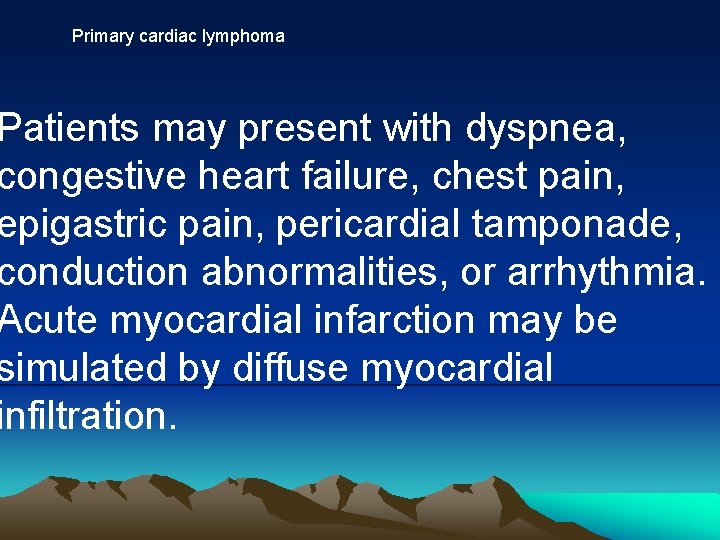

Primary cardiac lymphoma Patients may present with dyspnea, congestive heart failure, chest pain, epigastric pain, pericardial tamponade, conduction abnormalities, or arrhythmia. Acute myocardial infarction may be simulated by diffuse myocardial infiltration.